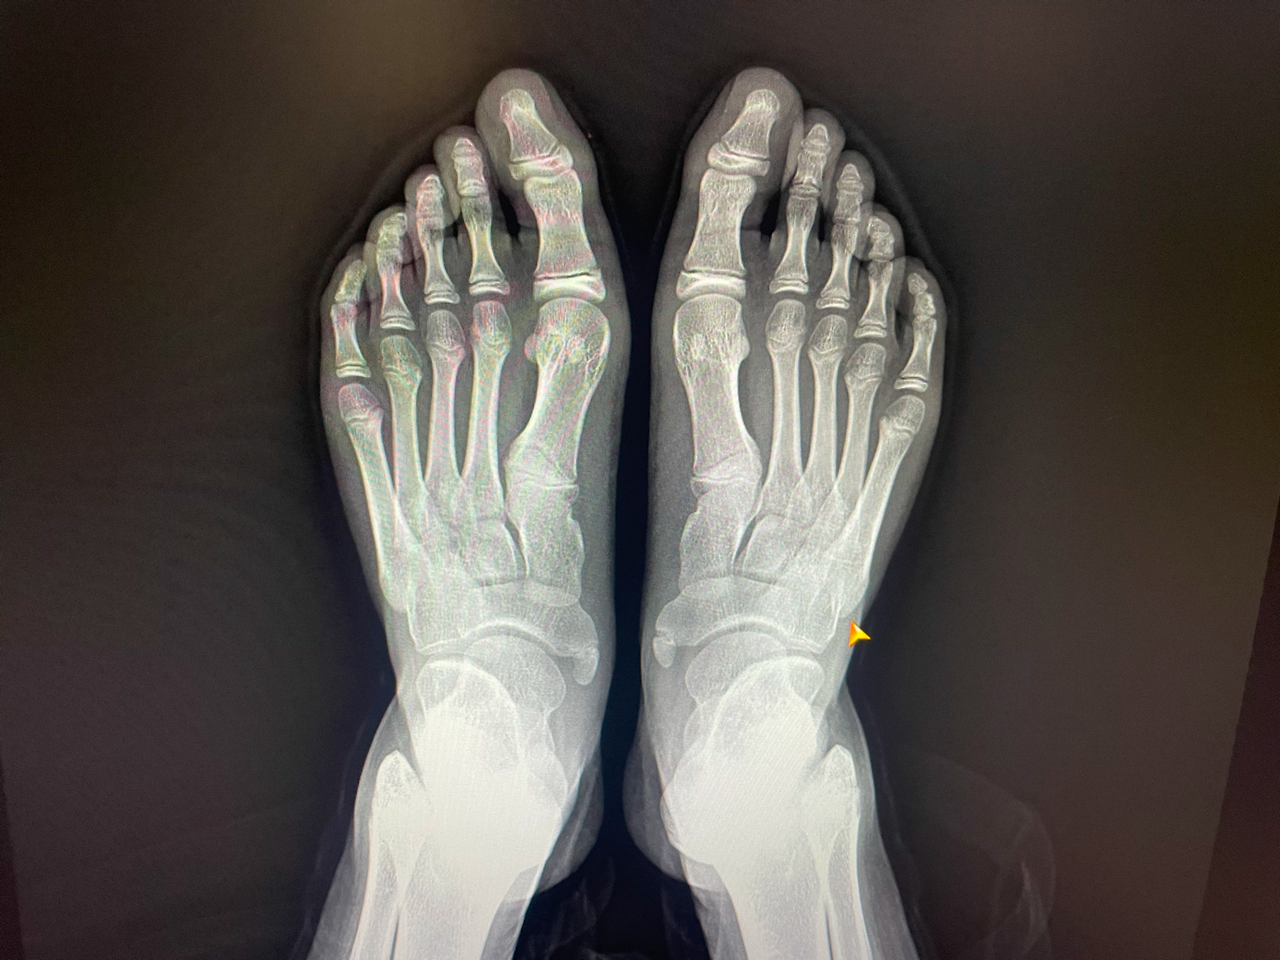

"어머니, 초롱이는 평발이에요."

"네?????? 평발이요?????"

평발이라고 하면 사실 발바닥에 아치가 평평하게 거의 펴져 있는 발이 평발이라 생각했다.

초롱이의 발은 외관상으로나 어디로 보아 평발은 전혀 아니었다. 그런데 선생님께서는 초롱이에게 평발이라고 하시니 놀라지 않을 수 없었다.

"초롱이가 보이겐 평발이 아니지만, 이렇게 옆에서 보면 다른 아이들보다 요기 이 부분의 아치가 거의 평발에 가까워요.

그리고 엄지발가락이 휘어 있는 것이 보이시죠? 그래서 자연스럽게 발을 땅에 디딜 때 발바닥부터 디뎌져야 하는데 그게 옆쪽이 먼저 닿게 되거나 그렇게 돼서 평소보다 많은 운동을 하거나 무리하거나 하면 이렇게 통증이 생기는 거예요.